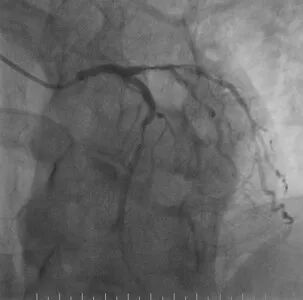

心脑联合造影

-- 右侧颈内起始部中度狭窄,经前交通向左侧代偿

波科支架怎么样​径技·第165期|7F经桡入路下的颈动脉狭窄支架成形术一例_https://www.jmylbn.com_新闻资讯_第18张

波科支架怎么样​径技·第165期|7F经桡入路下的颈动脉狭窄支架成形术一例_https://www.jmylbn.com_新闻资讯_第19张

波科支架怎么样​径技·第165期|7F经桡入路下的颈动脉狭窄支架成形术一例_https://www.jmylbn.com_新闻资讯_第20张

-- 冠脉多发狭窄